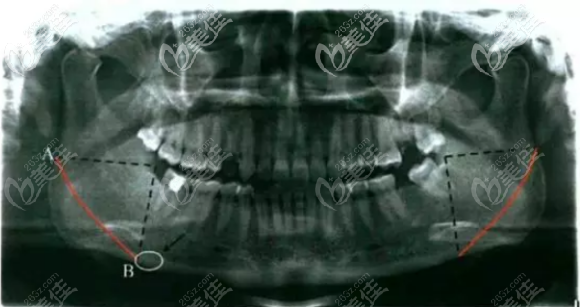

先拍x光片和曲面斷層片,還有三維成像ct,這些是用來判斷神經(jīng)和血管走位方向的,并且用來制定手術方案,如果患者符合做手術,然后安排住院。

從口腔內(nèi)側接近下頜角的的位置做切口,然后把下頜角處的皮膚和肌肉翻開,之后把多余的外板去除,打磨,再按照事先設計好的磨骨量,截掉多余的下頜角,接著取出骨塊,然后再進行一次打磨,這是為了讓線條更加流暢,隨后進行縫合和包扎。